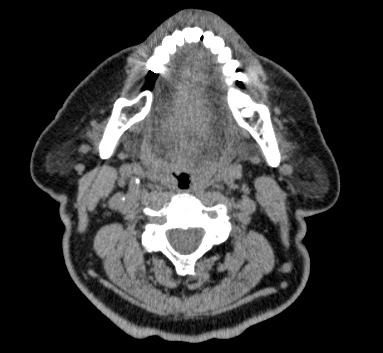

Мультиспиральная компьютерная томография – это высокоинформативный лучевой метод диагностики различной патологии мягких тканей шеи, включая воспалительные заболевания, травматические повреждения и опухолевые процессы. КТ позволяет оценить состояние щитовидной железы, паращитовидных желез, гортани, верхней части пищевода, шейных лимфоузлов и окружающих мягких тканей.

Метод КТ основан на применении рентгеновского излучения. Однако в отличие от обычного рентгена, при котором снимки производятся в одной плоскости, при КТ излучатель рентгеновских лучей постоянно двигается вокруг объекта исследования, проводя сканирование в различных плоскостях, а затем трансформируя полученные данные в цифровые трехмерные изображения. Это дает возможность визуализировать органы и ткани в мельчайших подробностях, а с помощью объемных 3D-реконструкций наглядно оценить пространственное расположение органов и патологических образований.

Рентгеновские лучи лучше всего поглощаются плотными структурами, такими как костная ткань. Поэтому кости хорошо видны на снимках КТ. Это делает компьютерную томографию незаменимой при необходимости обследования, в частности, костного скелета гортани. Однако для улучшения визуализации мягких тканей требуется введение специального контрастного препарата, поэтому КТ мягких тканей шеи в подавляющем большинстве случаев проводится с контрастным усилением.

Для контрастирования используется йодсодержащее контрастное вещество, которое в составе рентгеноконтрастного препарата вводится в вену пациенту непосредственно во время исследования. Благодаря способности контраста поглощать рентгеновские лучи на снимках КТ хорошо контрастируются кровеносные сосуды и опухолевые образования, имеющие, как правило, развитую сосудистую сеть. Методика внутривенного болюсного контрастирования помогает обнаружить воспалительные изменения, отличить доброкачественные опухоли от злокачественных, выявить поражение лимфатических узлов и степень прорастания опухоли в магистральные сосуды и окружающие ткани.